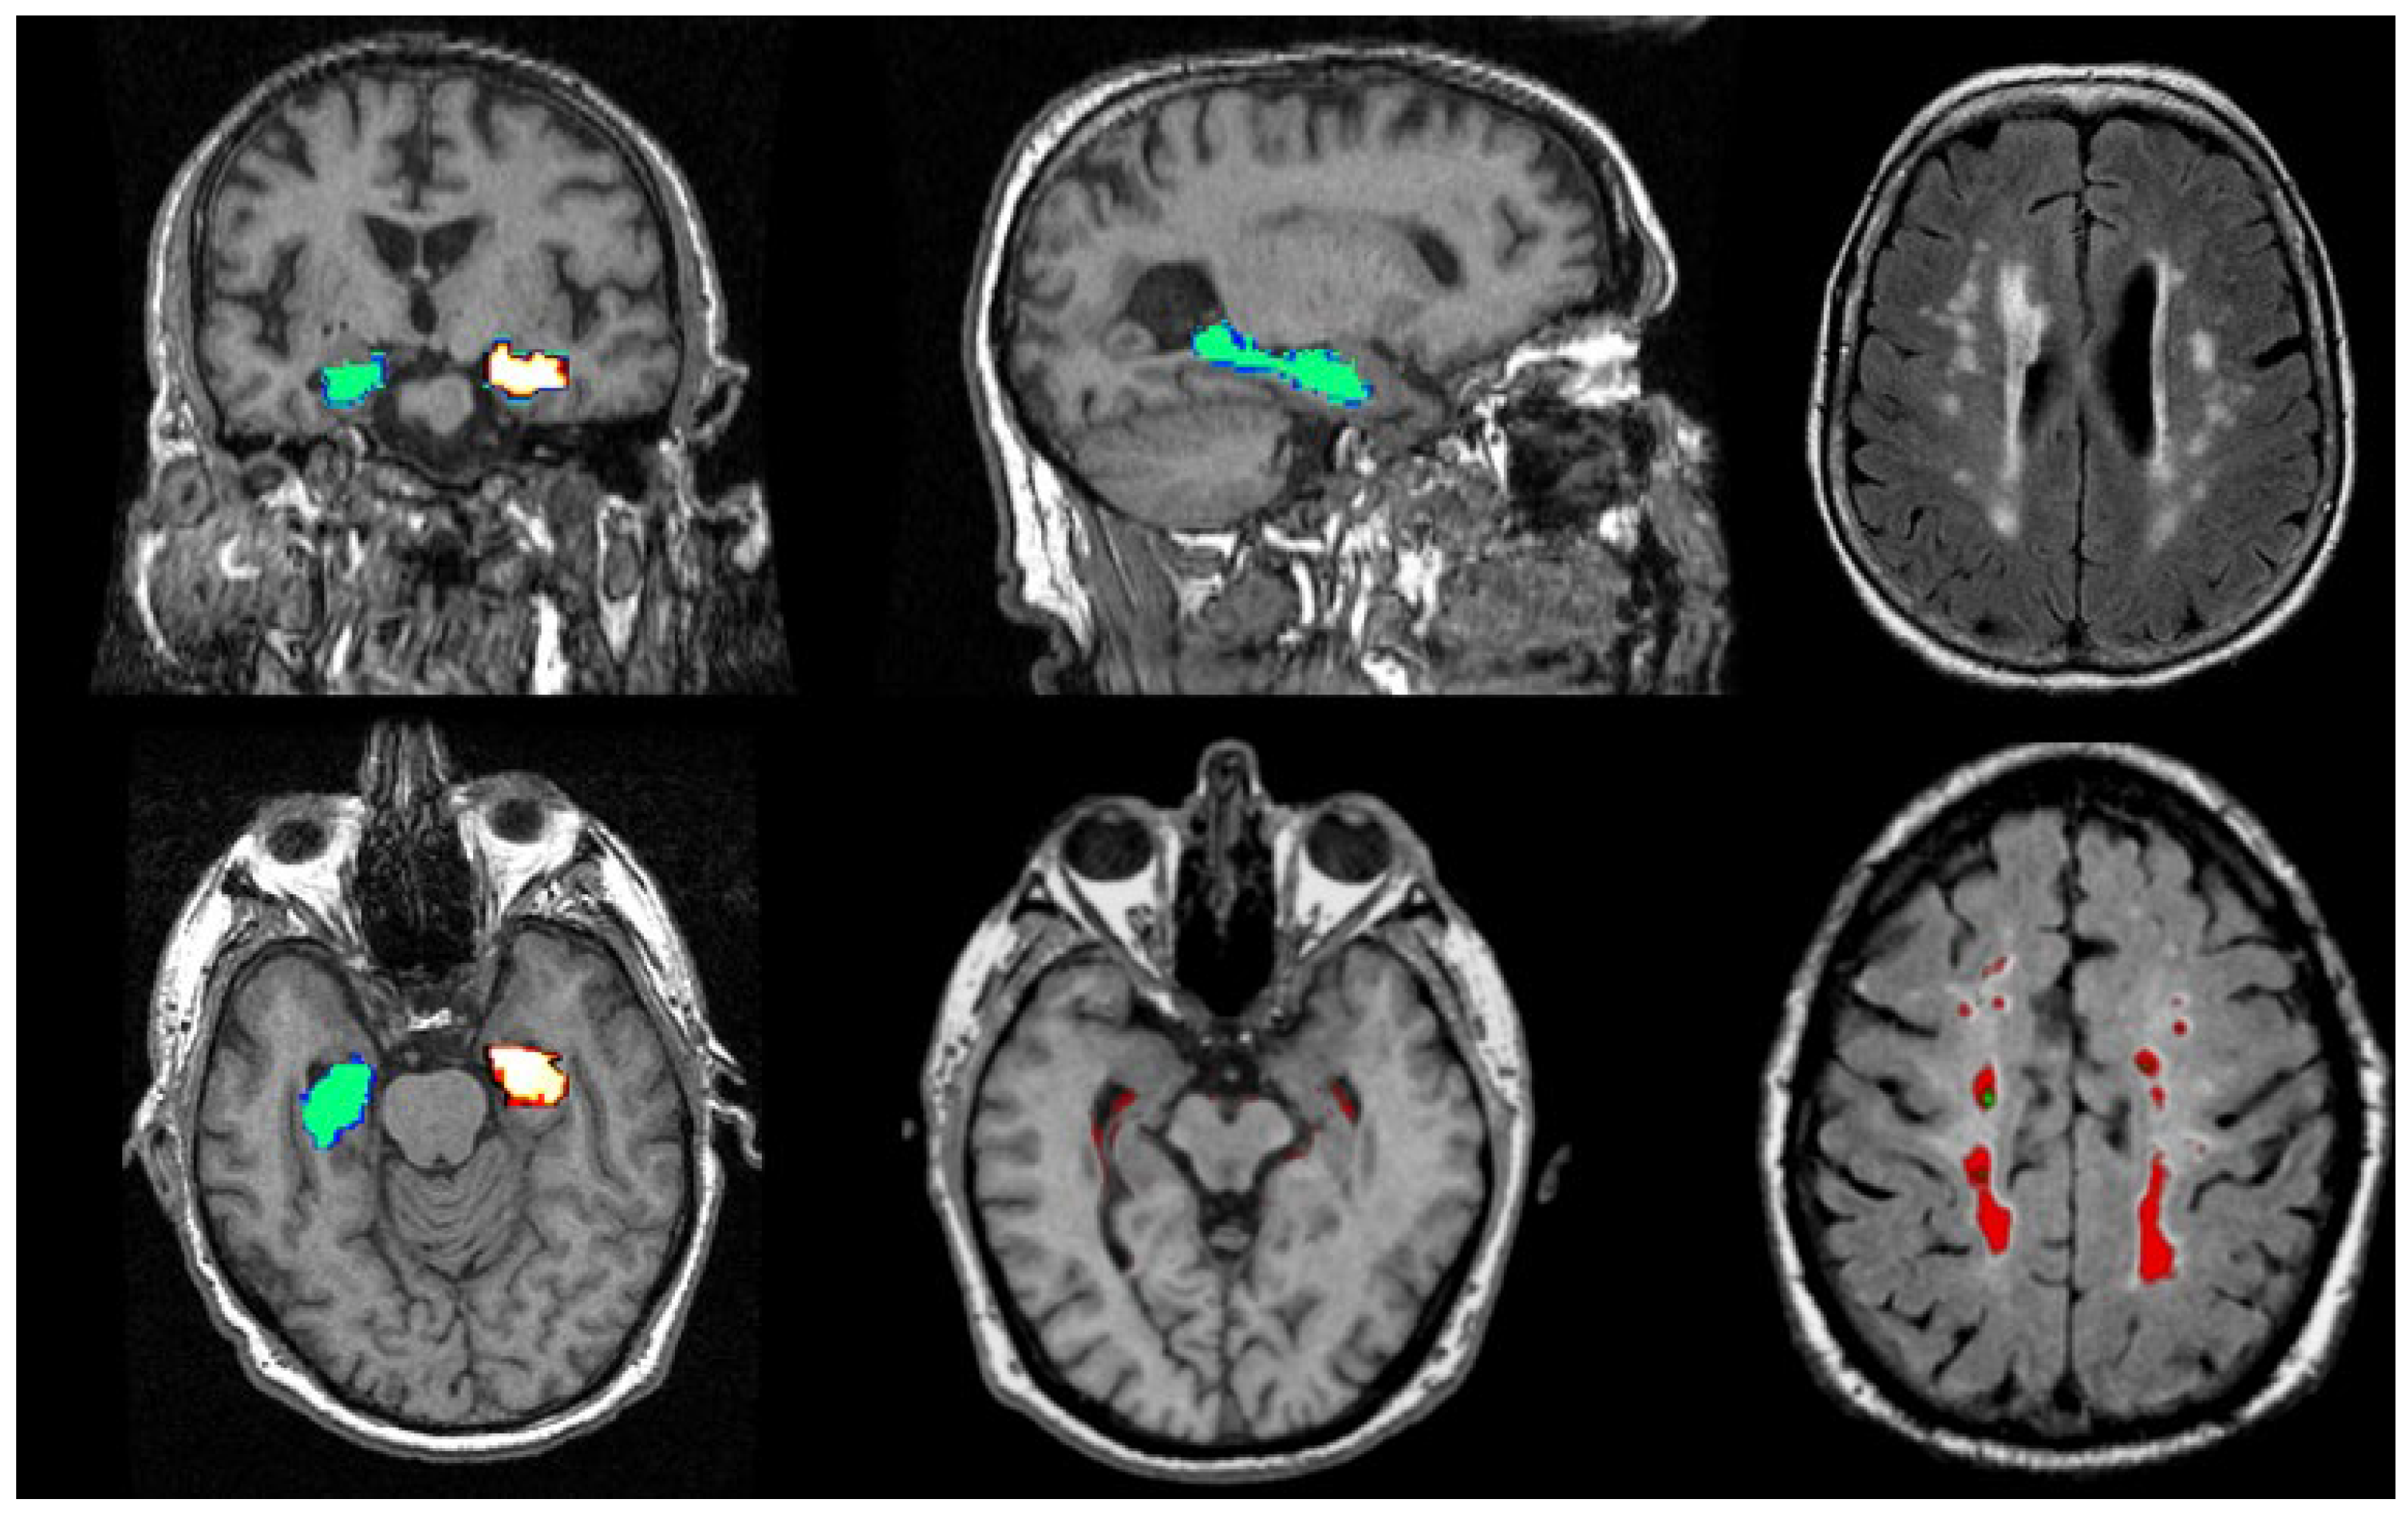

Figure 6.

Illustrations of MRI biomarkers in AD showing hippocampal volume (green and golden) in participants from the Aberdeen Birth Cohort 1936 study, illustrating hippocampal volume measurement (top row: left and centre; bottom row: left and centre), and white matter hyperintensities (top row: right, bottom row: right) in white and red. (Courtesy—Alison D. Murray, University of Aberdeen).